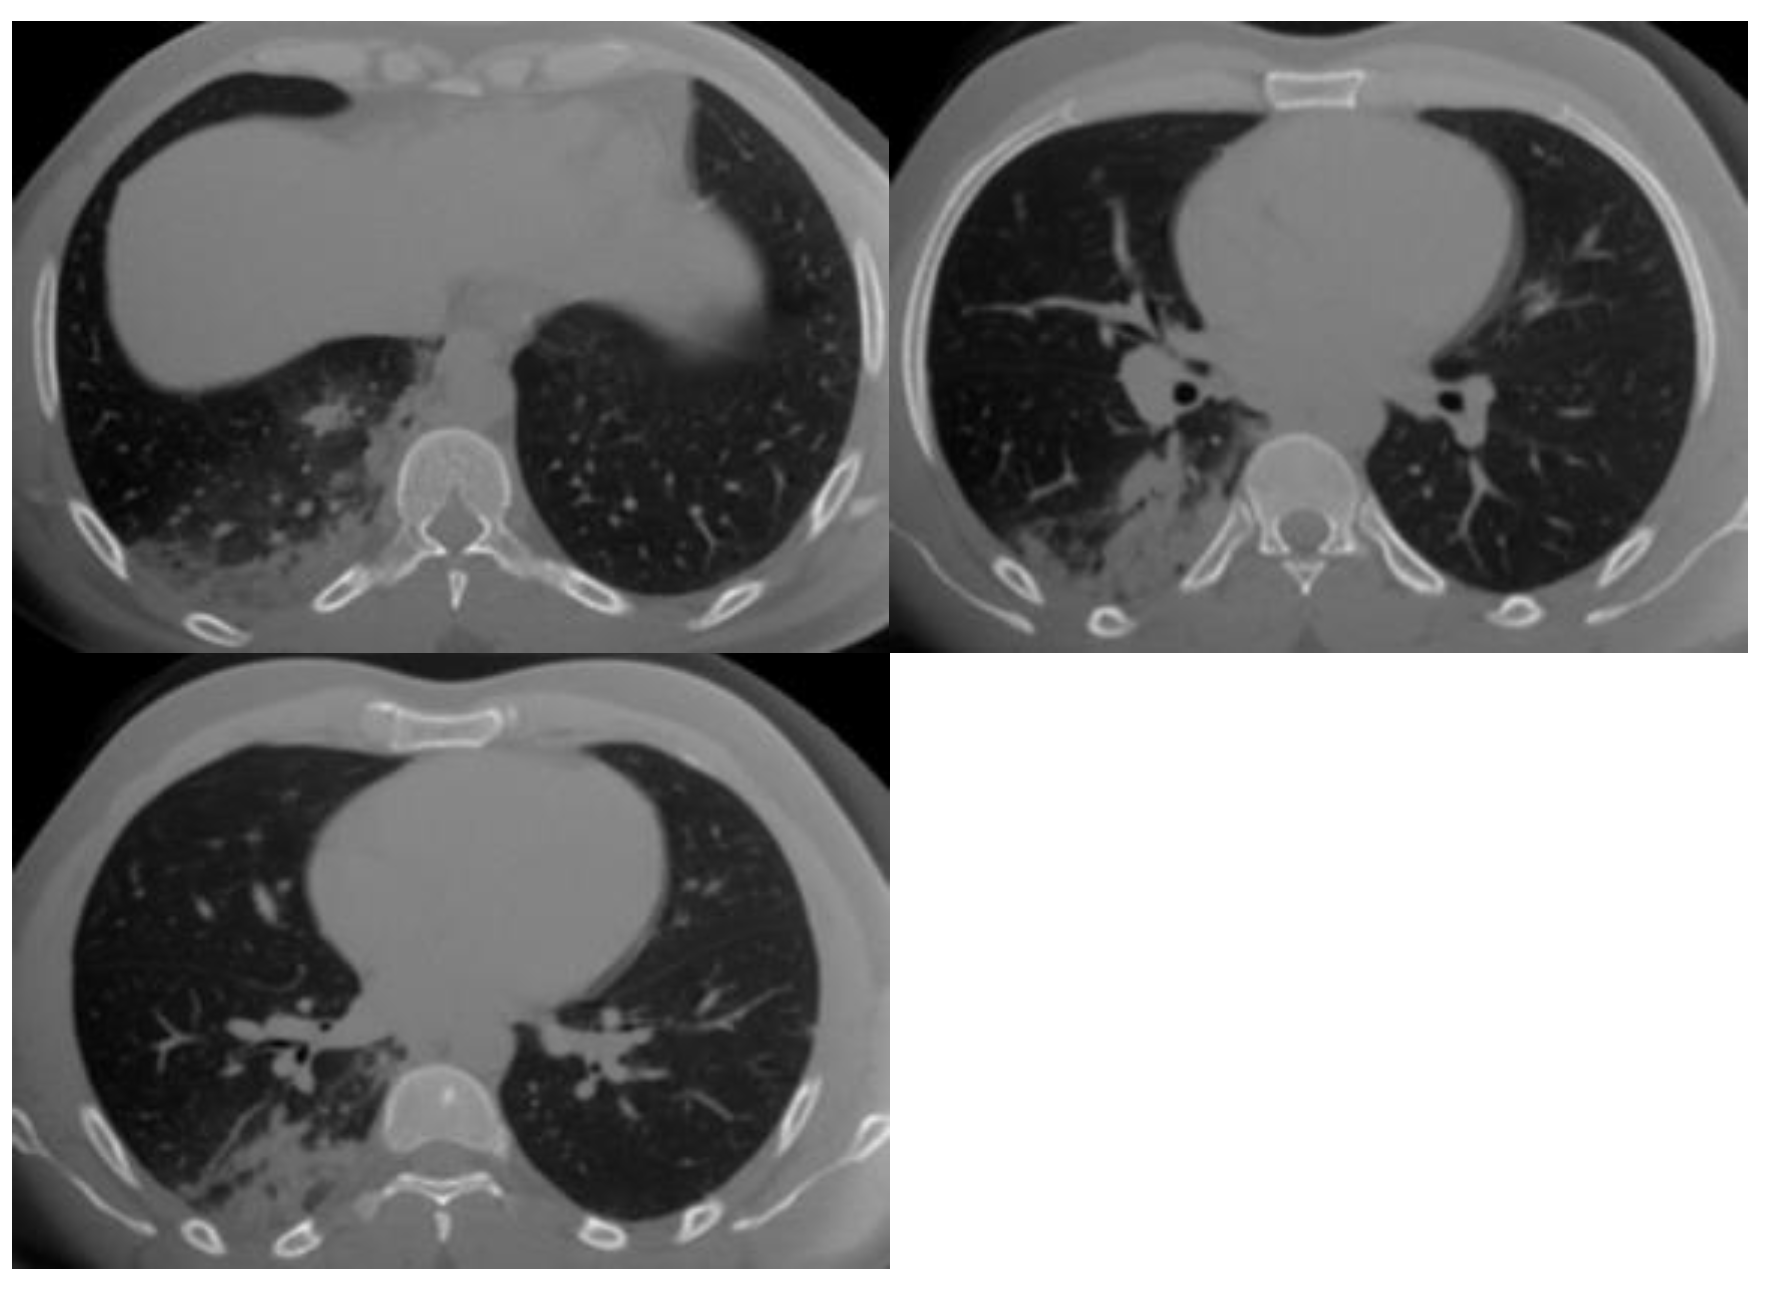

| 4 | High | CT findings are similar to those for CO-RADS 5, but a lack of contact with the visceral pleura, located unilaterally, in a peri-broncho vascular distribution, or when the findings are superimposed on pre-existing lung abnormalities. |